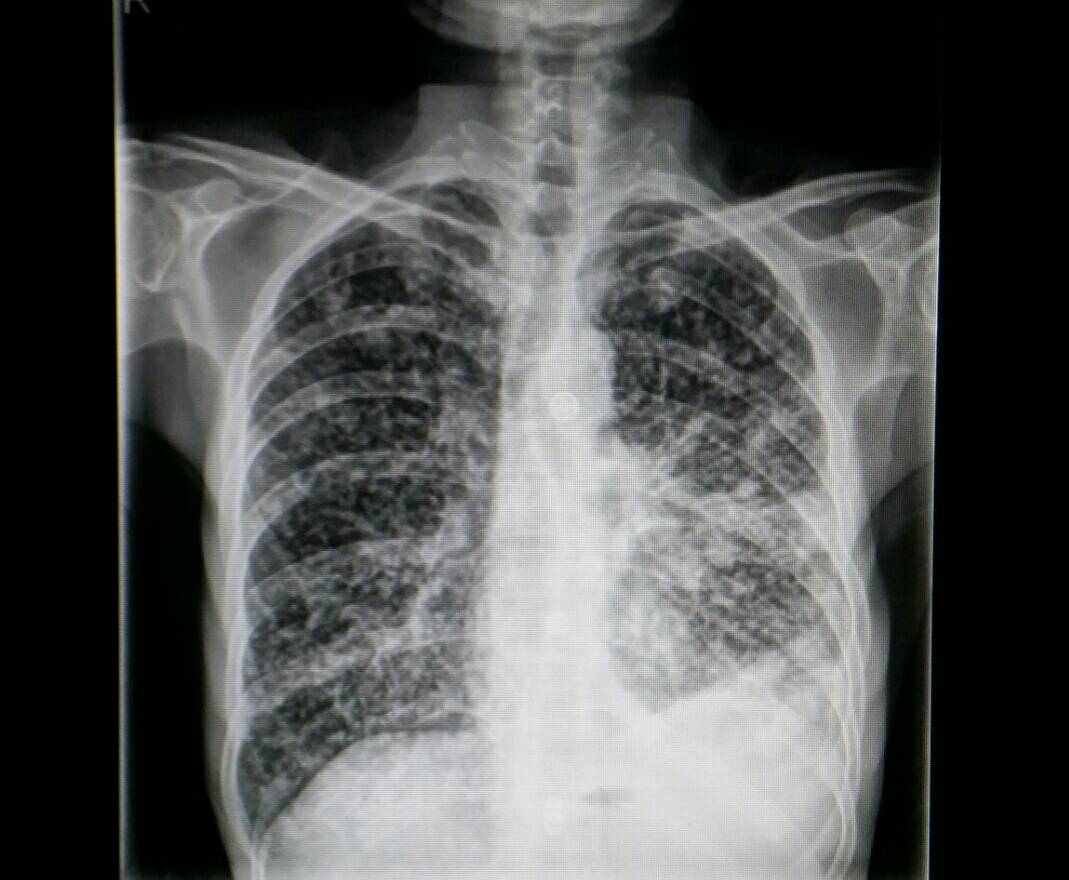

答案公布前第一位答对且分析有理有据者者获1000积分!答案将于一周后公布 恭喜manbuyunduan医生,您是以第一位答对并且补充了详细说明,获得1000积分奖励!也特别感谢圣艮山先生提供这么好的病例给大家讨论,开拓思路,因此也同时赠送1000积分! 周XX,男,20岁    主诉:反复发热、皮疹3月余 入院情况:患者2009年1月底汗出受风后出现双膝粟粒样红色皮疹,高于皮面,压之退色,伴瘙痒,当时无发热、肌肉关节痛等,当地医院予脱敏治疗后皮疹消退,几天后病情反复同前,改予阿奇霉素治疗5天症状再次好转。 约1周后无明显诱因出现左手中指、无名指近端指间关节疼痛伴肿胀,当地查类风湿因子阴性,予以氟轻松外用后肿痛减轻。此后先后又出现右手腕关节、双肘关节疼痛,皮温皮色均无异常,关节局部无肿胀。 2月7日开始无明显诱因反复发热,时伴畏寒、寒战,体温最高曾达41℃,伴周身散在皮疹同前,四肢肌肉酸痛,踝关节、腕关节、肘关节间断疼痛,退热治疗后体温下降,皮疹随之消退,关节肌肉酸痛减轻。外院查血常规:WBC明显升高(数值不详),予以抗感染、外用三九皮炎平并配合自制中成药治疗,体温高峰有所下降,但仍反复发热、以中度发热为主,伴周身散发皮疹。 3月中旬上述症状加重,肌肉酸痛明显,在当地医院查血常规:WBC 20.3×109/L,N 87.9%;肝全:ALT 84U/L,AST 37U/L,4ALB 33g/L;抗结核抗体阴性;ESR 46mm/h;CRP 22.8mg/L;ANA核仁型1:320,抗Sm 13.5KD(+),抗RNP 32KD(+),抗SSA 52KD(+),抗Jo-1(+);类风湿因子阴性;抗CCP抗体阴性;IG、补体、ASO均未见异常。予静脉应用甲基强的松龙40mg Bid*4天,期间体温恢复正常,皮疹基本消退,肌肉及关节酸痛消失。后激素减为强的松60mg Qd*3天,因症状反复停药出院。